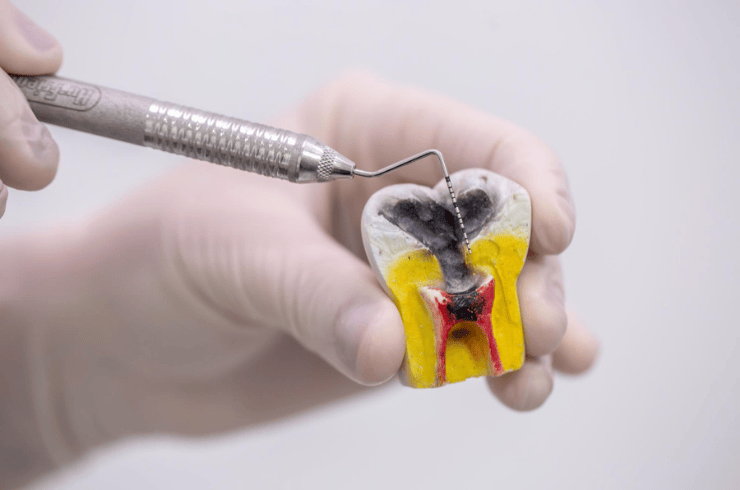

Pain-relieving treatment to save infected teeth and prevent extraction.